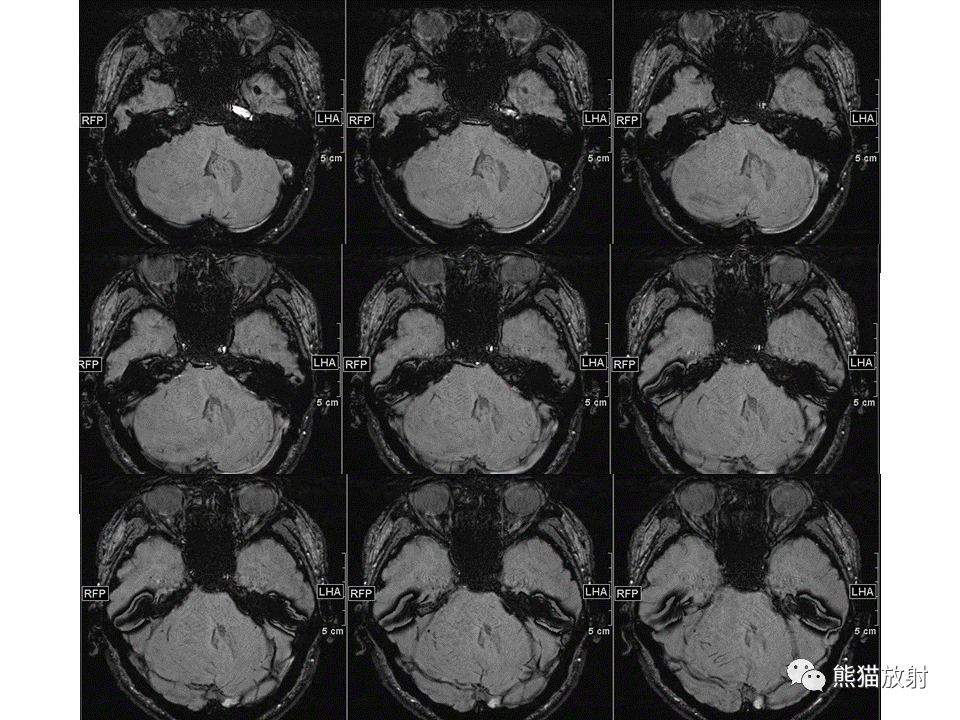

【PPT】小脑发育不良性神经节细胞瘤 VS 成人型髓母细胞瘤-1